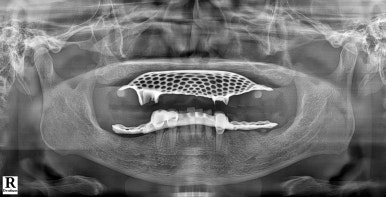

좌: 틀니를 착용하고 엑스레이를 찍은 모습, 우: 풀아치 임플란트를 식립한 직후 (2024년 7월 1일)